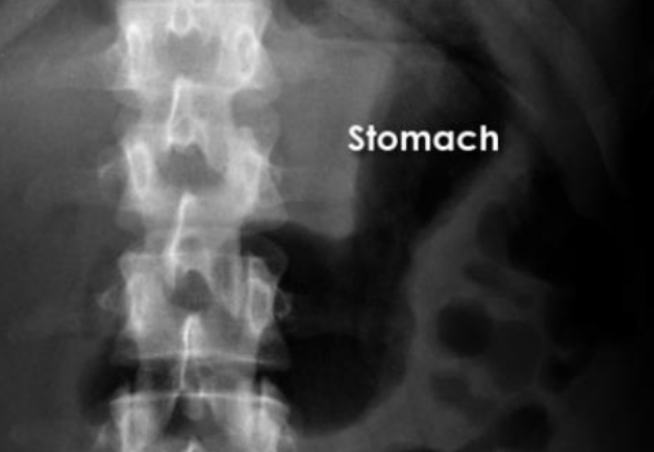

What is this and what type of scan

Stomach, AXR